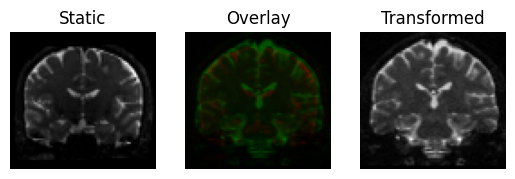

This produces a slight rotation, and the images are now better aligned

Registration result with a rigid transform, using Mutual Information.